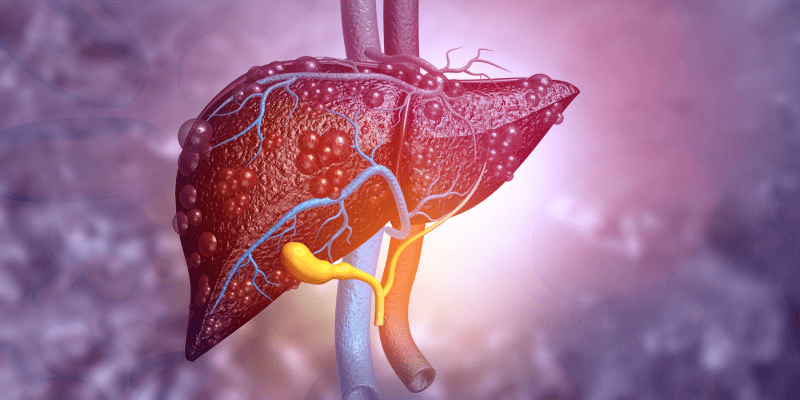

While liver cancer is the third deadliest cancer in the world, there are still unmet needs regarding the disease.Kerri FitzgeraldBile Duct Cancer | April 22, 2020

The U.S. Food and Drug Administration approved Opdivo® (nivolumab) in combination with Yervoy® (ipilimumab) for ...Kerri FitzgeraldColorectal Cancer | February 11, 2020